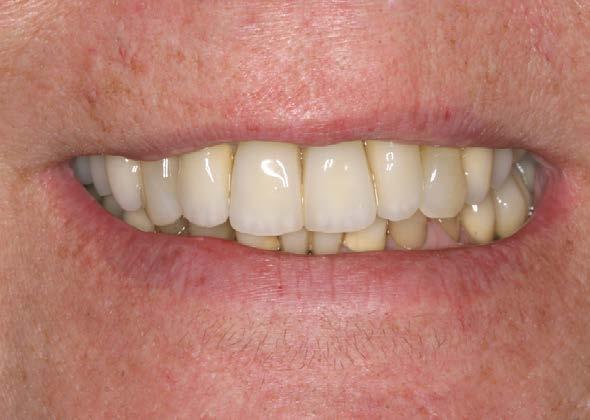

La paciente continúa en seguimiento. A los 8 años, la estabilidad de los tejidos duros y blandos, así como la estética de la rehabilitación, era completa (Figura 9-11). A los 12 años se observó

una buena progresión del tratamiento, sin cambios reseñables (Figura 1214). A los 20 años de seguimiento se constató una evolución estable, sin pérdida ósea en dientes ni implantes, y con buena salud de los tejidos periimplantarios (Figura 15-17).

Figura 8. Imagen de sonrisa con la prótesis finalizada.

observaron diferencias clínicas significativas entre estas configuraciones en cuanto a pérdida ósea o comportamiento tisular, lo cual se ve claramente reflejado en este caso clínico con seguimiento a largo plazo.19-21